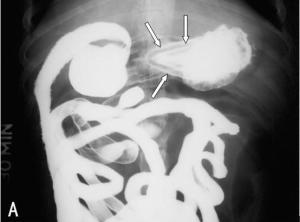

小肠内异物多为误吞或故意吞服的各种物品,前者多见于儿童、精神异常或戴义齿者,后者多见于企图自杀者。可出现腹胀、便秘,甚至呕吐;异物刺入或嵌入肠壁,可引起腹痛、感染和发热;异物损伤肠黏膜,可引起溃疡和出血。[1]